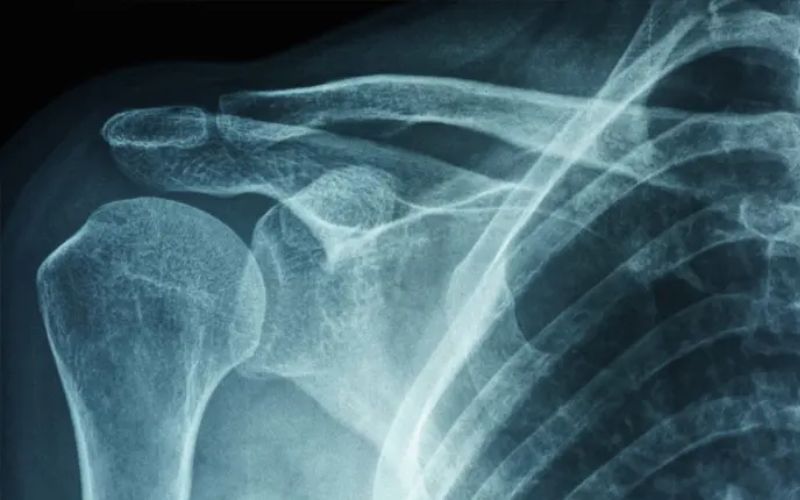

Vòng bít rotator gồm nhóm cơ và gân giữ vai ổn định. Khi nhóm này bị rách nhẹ hoặc viêm do vận động mạnh, cơn đau dễ xuất hiện vào buổi sáng. Gân bị tổn thương nhạy hơn khi chịu áp lực trong lúc ngủ. Người chơi thể thao hoặc nâng tay lập lại dễ gặp tình trạng này. Khi nằm đè lên vai trái, gân bị kéo thêm và gây ra ngủ dậy bị đau bả vai trái.

Ảnh minh hoạ

Cơn đau do vòng bít rotator thường âm ỉ nhưng tăng khi bạn xoay tay. Nếu bạn nghiêng người về bên trái trong lúc ngủ, vùng tổn thương bị ép mạnh hơn. Điều này gây đau nhiều khi bạn vừa mở mắt. Chấn thương nhóm gân này khiến vai yếu và dễ đau khi nằm lâu một tư thế.